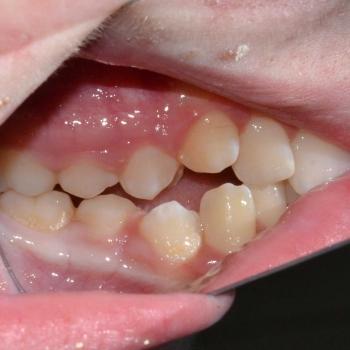

Kíra és édesanyja egy kollegám javaslatára kerestek fel a rögzített fogszabályzó számára legoptimálisabb időszakban, a tejfogak leváltása után, de még a 7-es fog előtörése előtt. Az első konzultáció alkalmával fény derült az alsó és felső fogív nagymértékű torlódására, a jobb felső szemfog kiszorult helyzetére és következményes felső középvonal eltolódására, illetve az enyhe mélyharapásra. A röntgenek kiértékelése után ez a kórkép kiegészült az alsó és felső metszőfogak hátradőlt pozíciójával, ami a kezelést nagyban megkönnyítette, mert lehetőséget adott mindkét fogív meghosszabbítására, így helynyerésre a torlódott fogazat számára.